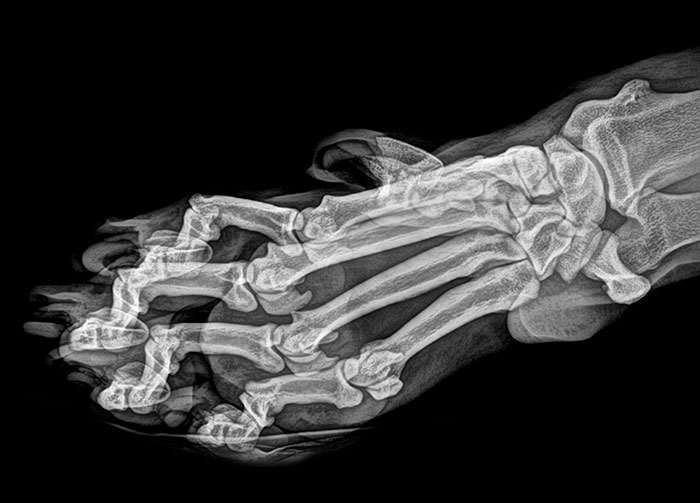

Идеальная ножка балерины в Х-лучах